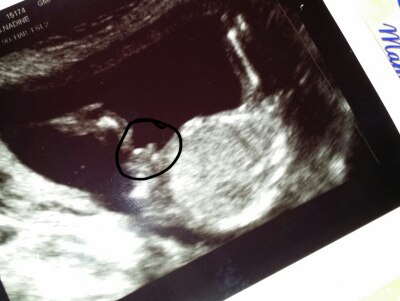

Hallo zusammen ! :) Ich war gestern beim Frauenarzt, zur normalen Vorsorge. Er machte einen Ultraschall und als ich nachfragte ob man denn jetzt schon sehen könne was es wird, hatte er nach langem suchen ( lag ziemlich ungünstig ) gemeint es wäre wohl eher ein Junge. Das wäre natürlich super weil ich jetzt schon 3 Mädels habe. Aber irgendwie kann ich das noch nicht so recht glauben. Wie sicher ist denn so ein jungenoutin bei 16+6 ? Ich häng hier mal ein Bildchen an...hab den "Schnippel" eingekreist. Wünsche euch noch einen schönen tag. LG Namima

Bild zu 17. Woche outing...wie sicher ? - Schwanger - wer noch? Rund um die Schwangerschaft